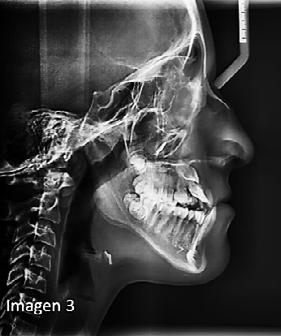

b) Análisis radiográficos, periapicales, ortopantomográficos, oclusales, lateral de cráneo, anteroposterior de cráneo.

c) Estudio y análisis tomográfico en tercera dimensión del cráneo a nivel maxilar y mandibular (Figura 24).

d) Fotografías intra y extraorales.